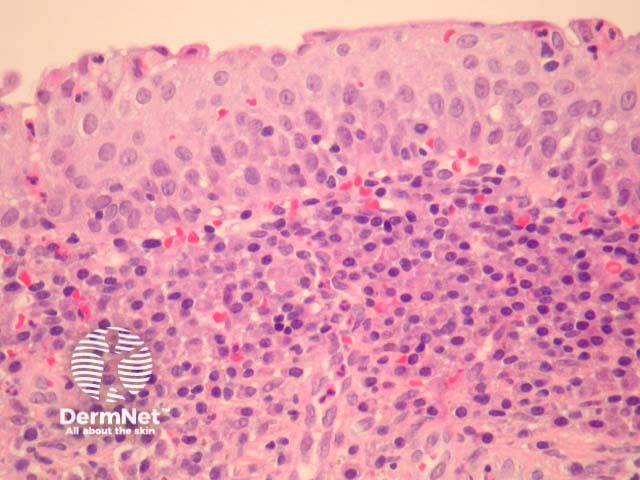

In Zoon balanitis/vulvitis, sections show mucosa which may be attenuated or eroded overlying a dense stromal infiltrate (figures 1,2). The infiltrate contains numerous plasma cells which often form sheets. There may be fewer eosinophils and neutrophils. Vascular ectasia and extravasated erythrocytes are common (figures 1,2,3).

Figure 1